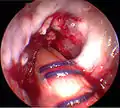

![]() آرتروسکوپی رباط صلیبی قدامی جهت بازسازی مجدد در زانوی سمت راست پس از پایان جراحی بازسازی رباط آسیب دیده نشان داده شدهاست. ۱- تاندون[پ 1] ماهیچه سمیتندنیوس[پ 2] که چندلا شده و با ضخامتی مناسب به سمت بالا کشیده شدهاست. ۲- اتوگرافت[پ 3] از جلوی رباط متقاطع پشتی[پ 4] به سمت بالا کشیده شدهاست. ۳- رباط[پ 5] تازه که از مسیر قبلی رباط آسیبدیده عبور کرده و جایگزین آن شدهاست. | |